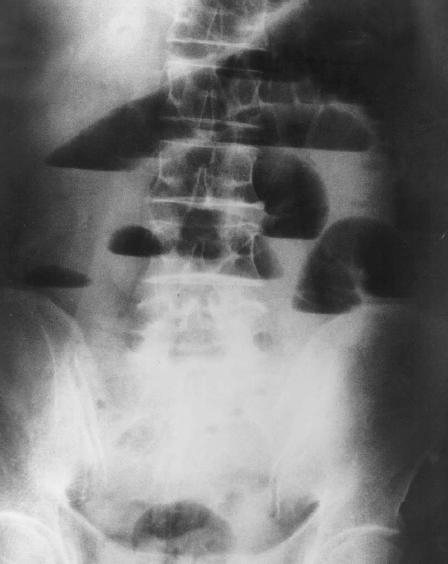

Image hydro -aerique en

escalier et sa largeur est tres etroite que la

hauteur . Occlusion de l'intestin grele , |

| Occlusion du

colon : Les images hydro-aerique se situe autour de

l'abdomen et sa hauteur est de plus de la largeur . |